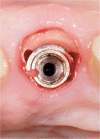

Introduction: Dental implants have become a standard treatment in the replacement of missing teeth. After tooth extraction and implant placement, resorption of buccal bundle bone can pose a significant complication with often very negative cosmetic impacts. Studies have shown that if the dental root remains in the alveolar process, bundle bone resorption is very minimal. However, to date, the deliberate retention of roots to preserve bone has not been routinely used in dental implantology.

Conclusion: Whilst the socket-shield technique potentially offers promising outcomes, reducing the need for invasive bone grafts around implants in the aesthetic zone, clinical data to support this is very limited. The limited data available is compromised by a lack of well-designed prospective randomised controlled studies. The existing case reports are of very limited scientific value. Retrospective studies exist in limited numbers but are of inconsistent design. At this stage, it is unclear whether the socket-shield technique will provide a stable long-time outcome.